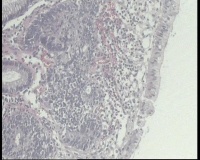

横结肠中部见一增生性肿物大小2.0x1.5厘米,表面糜烂充血,取材2块

2块组织内有1块正常,另一块局灶腺体异型,细胞复层排列,细胞核异型不太大,局灶够高级别吗?